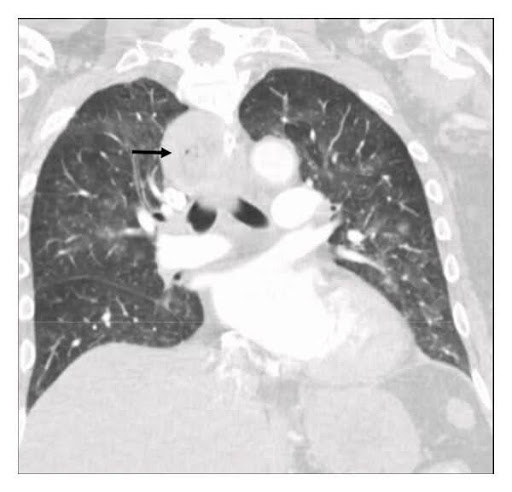

Fig. 2: CT thorax1

Here, an almost complete atelectasis of the left lower lobe and a distended oesophagus were seen. The next step was a gastroscopy to get to the bottom of the matter.